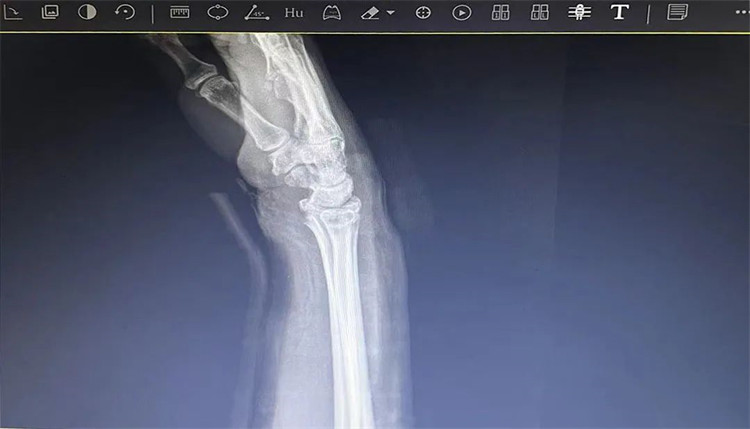

患者老年女性,50多歲,在騎電動車停下時因電動車倒下,右手著地,當(dāng)即感覺,右腕及骶尾部腫痛伴右關(guān)節(jié)畸形、活動受限,急來我院就診。門診醫(yī)師結(jié)合病史、查體及輔助檢查后,診斷為:右橈尺骨遠(yuǎn)端骨折、骶尾部挫傷并收入住院部。

患者入院后,中醫(yī)正骨科副主任鄭斌斌,認(rèn)真查體及分析檢查結(jié)果后,考慮患者老年女性,建議患者采用拔伸牽引、端提、捺正等閉合手法復(fù)位后,行夾板固定,多能獲得較好療效?;颊邚?fù)位固定后,疼痛明顯減輕。避免了手術(shù)帶來的痛苦及手術(shù)開刀所需費(fèi)用。